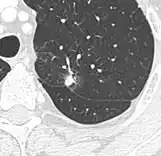

- Vascular convergence is where vessels converge to a nodule without adjoining or contacting the edge of the nodule, and is mainly seen in peripheral subsolid lung cancers.[9] It reflects angiogenesis.[9]

Air bronchograms is defined as a pattern of air-filled bronchi on a background of airless lung, and may be seen in both benign and malignant nodules, but certain patterns thereof may help in risk stratification.[9]